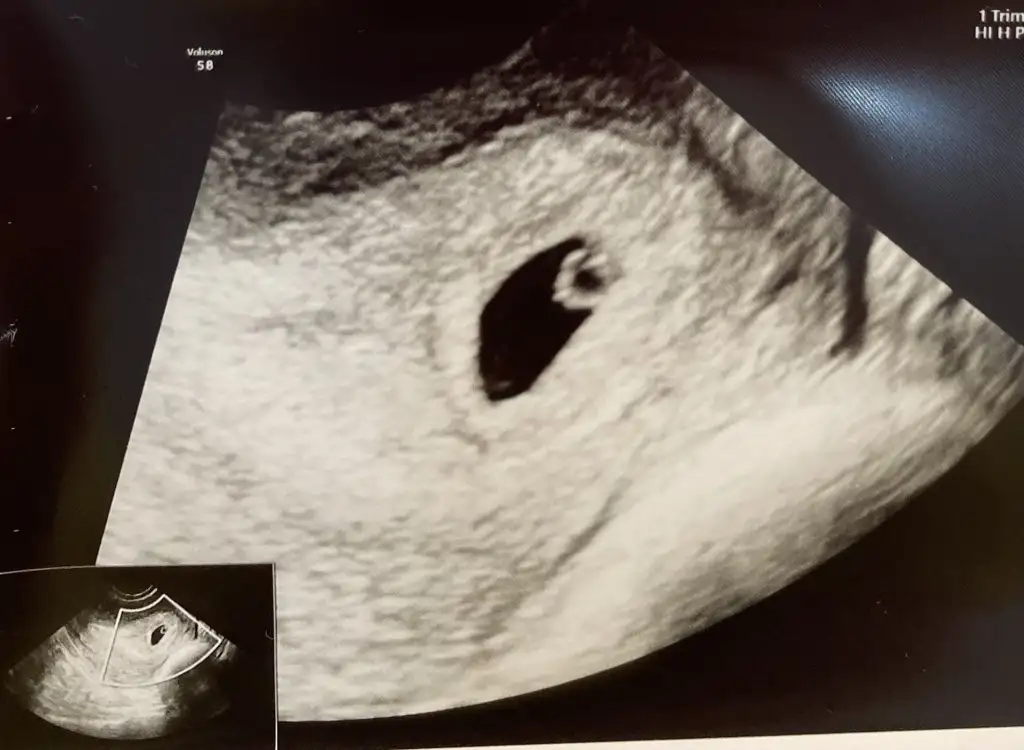

Önemli olan bebek değil canım plasenta ve kız diyorum. Ramziye göre de bebek şekline göre de kızEki Görüntüle 3261039

Aynen kıpırdattokca kese seklı degısıyor, ben de keseye gore tahmını saglıklı bulmuyorumBen söyledim, keseye pek inanmıyorum ama ultrasondan ultrasona değişiyor . Benin bazı ultrasonlarda yuvarlak bazılarında ince uzun çıkıyor değişiyor nedense. O yüzden erkek diyorum ramziye göre de erkek![]()

Sağlıklı olsunlar da bizimki işin heyecan ve eğlence kısmıAynen kıpırdattokca kese seklı degısıyor, ben de keseye gore tahmını saglıklı bulmuyorumbakalım ne cıkıcak cınsıyet